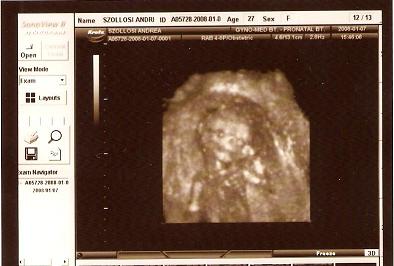

Nagyon édesek a bébik!!!

Kriszti: a középső képre akartam neked írni, hogy tiszta Levente, mikor rájöttem, hogy naná, hogy tiszta levenet

. Nagyon édes!!! Még szép, hogy édes mivel Levente!